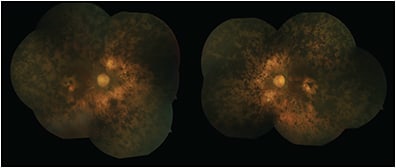

Enhanced S-cone syndrome, also called Goldmann-Favre syndrome, is an autosomal recessive vitreoretinal degeneration related to mutations in the NR2E3 gene, also called photoreceptor-specific nuclear receptor (PNR).12,13 Patients present with night blindness and visual field deficits. Fundus examination typically shows nummular pigmentary deposition at the level of the RPE along the vascular arcades (Figure 3),14,15 and in more severe cases, it may show fibrillar vitreous degeneration, chorioretinal atrophy, a sharply demarcated circumferential pigmentary retinal degeneration, macular and/or peripheral retinoschisis, presenile cataracts and hyperopia.13,16